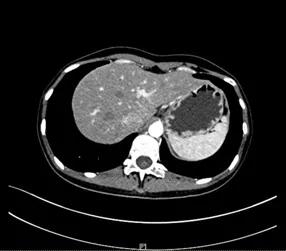

对于胃癌患者而言,胃镜检查是一个重要组成部分,它能直观地显示患者肿瘤病灶的情况。而为了判断肿瘤病灶的浸润程度以及有无转移情况,我们还需要进行胸腹盆增强CT检查,必要时还需要借助PET-CT来全面评估。我们给这位患者安排了增强CT检查,非常幸运,CT影像提示患者的肿瘤病灶属于早期阶段,从CT上并没有看到有淋巴结或者其他器官肿瘤转移的情况,同时各项抽血化验指标也提示,这位女患者的身体情况可以耐受手术。在听到自己的CT结果提示没有肿瘤转移时,这位患者难得的高兴了一阵子。但是我们不敢掉以轻心,在真正进行手术前,一切都是未知数。我们向患者充分告知了手术风险后,准备给她安排腹腔镜远端胃癌根治术。

术前CT检查